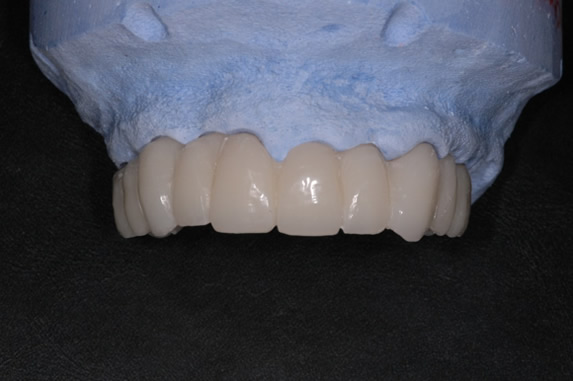

Fig.3 e 4  In questo modo possiamo costruire un provvisorio in resina che abbia già delle informazioni sull’estetica finale desiderata dal paziente